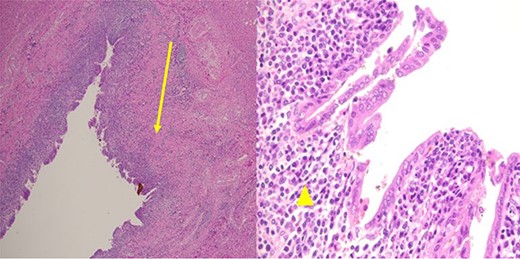

A 35-year-old man presented with a history of recurrent episodes of epigastric pain. Ultrasonography revealed an intrahepatic cyst (Fig. 1), and magnetic resonance cholangiography revealed that the cyst was connected to the cystic duct and right anterior sectoral bile duct (Fig. 2). The patient underwent an endoscopic retrograde cholangiography, which showed that the contrast could fill the cyst (Fig. 3). The laboratory findings, including a complete blood count, showed a white blood cell count of 4200/mm3 (lymphocyte 23%, neutrophil 62%); haemoglobin level of 16 g/dL; platelet count of 215 × 103/ mm3; total protein of 7.8 g/dL; albumin of 4.3 g/dL; total bilirubin level of 0.68 mg/dL; serum aspartate aminotransferase level of 26 IU/L; serum alanine aminotransferase level of 29 IU/L and alkaline phosphatase level of 105 IU/L. Tumour markers, including alpha-fetoprotein, carcinoembryonic antigen and carbohydrate antigen 19–9 were within normal limits. Viral markers for hepatitis B and C were negative. Due to the preoperative diagnosis of a type VI choledochal cyst, with a differential diagnosis of cystic intraductal papillary neoplasm of the bile duct, the patient underwent laparoscopic right anterior sectorectomy to excise the cyst completely. During the operation, after identifying the cystic duct and taking down the fundus and body of the gallbladder from the liver bed, an intraoperative cholangiogram was performed via the cystic duct connected to the cyst. Right anterior sectorectomy was then performed (Fig. 4). The postoperative period was unremarkable, and the patient was discharged on the sixth postoperative day. Pathological examination revealed a cyst with a fibrous wall, dense chronic inflammatory infiltration, lined by columnar epithelium. Mild reactive atypia, associated with marked chronic inflammatory cell infiltration, was noted. No signs of epithelial dysplasia were observed (Fig. 5).

Pathological examination revealed a cyst with a fibrous wall (arrow), dense chronic inflammatory infiltration, lined by columnar epithelium (arrowhead). Mild reactive atypia, associated with marked chronic inflammatory cell infiltration, was noted. No signs of epithelial dysplasia were observed.